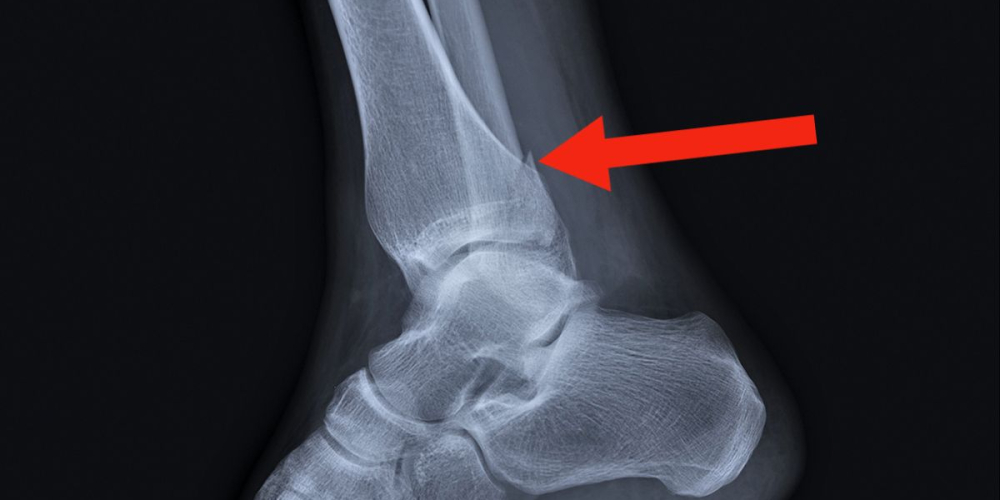

- Исследовать характер травмы голеностопного сустава позволяет рентгенологическое обследование. В процессе диагностики оценивается состояние целостности кости, смещение фрагментов.

- Компьютерная томография необходима для визуализации, уточнения позиции отломков, при оскольчатых, сложных, мелких перелом костей со значительным смещением и без.